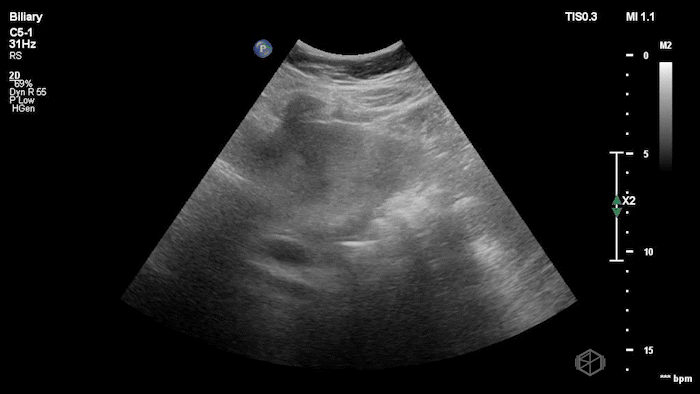

16 - What is the concerning finding?

Large mass near the neck of the gallbladder

16A - Same patient, what is the differential diagnosis for this finding?

Questionable stone-in-neck but, does not appear to be internal to the gallbladder; found to be gallbladder carcinoma.